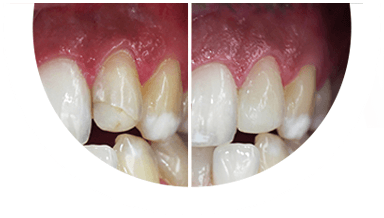

Paciente de 76 anos do sexo masculino

Motivo da consulta: Paciente desdentado total, procurava colocar dentes.

Plano de tratamento: Colocação de 4 implantes superiores e 2 implantes inferiores. Confeção de uma barra superior e colocação de 2 locators® na parte inferior. Confeção de uma prótese superior e outra inferior removível, com encaixes na barra e locators®.

A escolha deste plano de tratamento deve-se ao facto de o paciente querer uma solução total, mas não completamente fixa, uma vez que não tinha muita destreza manual para higienizar uma prótese fixa. Desta forma, conseguiu uma solução bastante retentiva (devido aos encaixes) mas que consegue remover para uma higienização correta.